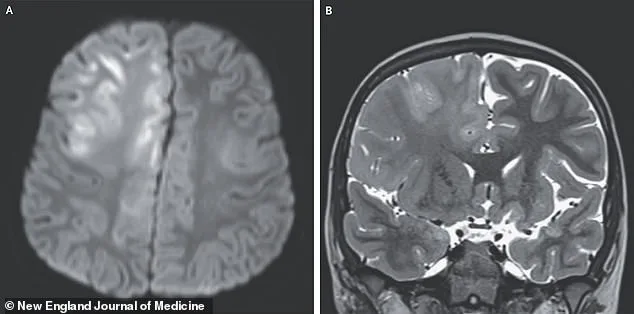

The boy's journey was marked by a cruel irony. His initial infection had been mild, yet the long-term consequences were catastrophic. An MRI scan of his brain revealed swelling and abnormal water molecule movement in the frontal lobe and corpus callosum, signs of cellular damage. The tragic outcome of his case serves as a stark reminder of the potential risks that lurk silently behind a seemingly benign infection. As SSPE progresses, patients typically descend into a vegetative state, with survival rates as low as 5 percent. The mortality rate for SSPE is a staggering 95 percent, and the few survivors often face years of suffering before death.